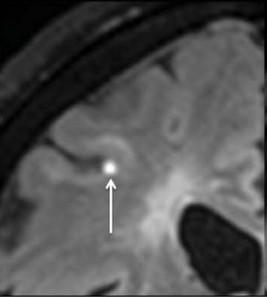

Chronic pathology within existing lesions slowly expanding/evolving lesions

Microglial activation

transfer ratio1, 7 Tesla MRI2 , Deformation-based (Jacobian) analysis using conventional T2- and T1- weighted images3 , susceptibility-weighted imaging (SWI)4 and quantitative susceptibility mapping (QSM)4